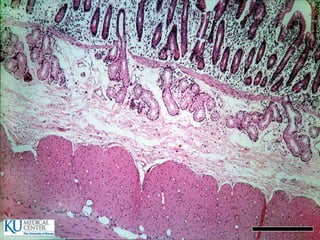

Intestino delgado  720cm de longitud  Duodeno: 20 cm  Yeyuno  Íleon

• 60.

Especializaciones superficiales de lamucosa  Pliegues circulares (válvulas de Kerckring)  Vellosidades y criptas  Microvellosidades  Tipos de glándulas:  Intestinales  Submucosas (Brunner)  Situadas fuera del tubo digestivo